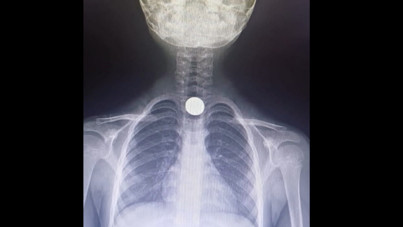

112 hekimi telefondan yönlendirdi, Heimlich ve kalp masajı yapıldı ama kurtarılamadı Düzce’de yemek sırasında nefes borusuna yiyecek kaçan 84 yaşındaki kadına, yakınları 112 Acil hekimi Dr. Ayşe Su Durkut’un telefonla verdiği talimatlarla Heimlich manevrası ve kalp masajı yaptı. Hastaneye kaldırılan yaşlı kadın, yoğun çabalara rağmen kurtarılamadı.

Otobüste korku dolu anlar! Şoförün müdahalesiyle hayatı kurtuldu Kocaeli Gebze'de, yediği cips nefes borusuna kaçan 3 yaşındaki çocuk, belediye otobüsü şoförü Ferdi Karabacak tarafından yapılan Heimlich manevrasıyla kurtarıldı.